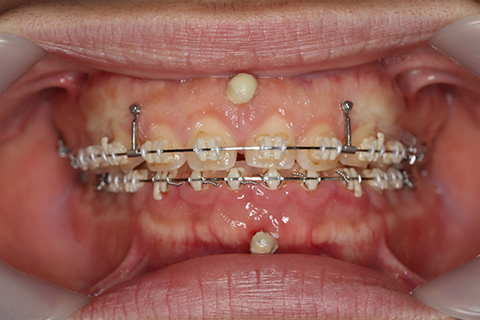

症例6(アンカースクリューを併用した矯正治療)

治療前

歯肉形成(形成)症例6(矯正用アンカースクリューで治療)治療前

治療中

歯肉形成(形成)症例6(インプラント矯正で治療)治療前

年齢・性別

24歳

治療期間

1年6ヶ月

抜歯

上下4番抜歯済み

治療費

80万円

備考

他院での矯正治療の不具合による再治療

治療内容

噛み合わせが深いのを改善するために前歯上歯肉に2本のスクリューを埋入して牽引。

施術の副作用(リスク)

疼痛、咬合時痛、知覚過敏、歯根吸収、歯肉退縮が生じる可能性があります。